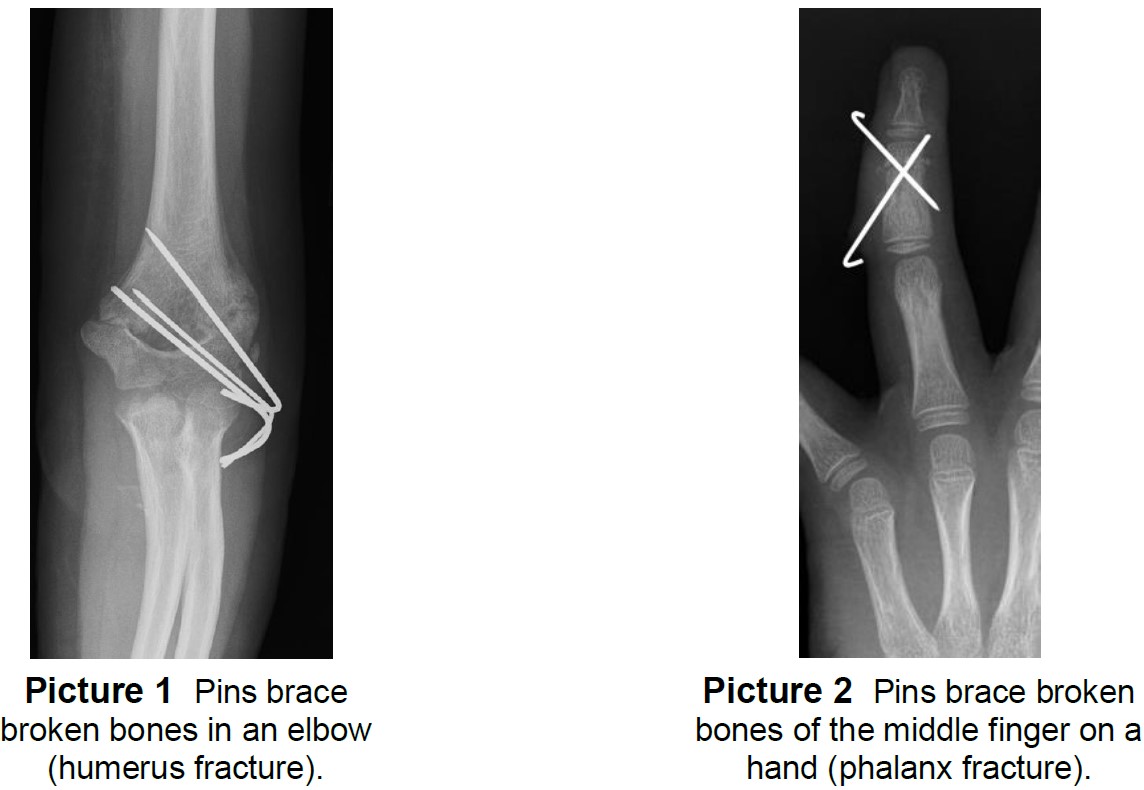

The doctor will need an x ray to evaluate the position of the broken finger bones.

Ring xray broken finger. If you have symptoms of a broken finger your doctor will likely obtain an x ray to determine if there is a fracture. Of ulna and radius bone x ray image of broken arm on monitor of pc. Finger intra articular fracture.

This x ray shows an oblique diagonal fracture through the proximal phalanx of the ring finger. Finger intra articular fracture. X ray is the primary tool used to diagnose a broken finger.

A broken or fractured finger occurs when one or more of these bones breaks. The finger series is comprised conventionally of a posteroanterior oblique and a lateral viewthe series examines in detail the distal middle and proximal phalanx as well as the interphalangeal metacarpophalangeal and carpometacarpal joints. X ray image of baby hand fracture holding mothers finger fracture shaft of proximal phalange of ring finger film x ray both hand ap x ray of broken finger.

Tap onoff image to showhide findings. A person with a fractured finger. With more complex injuries the doctor may seek the advice of an orthopedic bone and joint specialist or hand surgeon an orthopedic surgeon or plastic surgeon with post residency fellowship level.

The splint is typically worn for approximately three weeks and then removed. If a finger fracture is suspected then specific finger views are required rather than images of the whole hand. A typical fracture at the end of the small finger metacarpal is shown in this x ray.

Notice how the fracture tends to slip or shorten arrow. Not all fractures show up well on a single x ray so it may be necessary to obtain multiple x rays in different orientations if the diagnosis is unclear. This is an intra articular fracture of the ring finger middle phalanx.